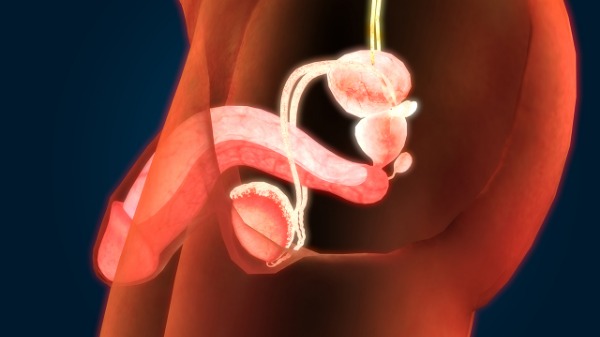

包皮手术是什么科

包皮手术通常属于泌尿外科,泌尿外科诊治泌尿系统及男性生殖系统疾病,包皮是男性生殖系统一部分,包皮过长、包茎等需手术时由泌尿外科医生操作,儿童包皮相关问题手术也多由其处理,成年男性因包皮过长致反复龟头炎等也需到泌尿外科就诊考虑手术,不同医院科室设置有细微差异,基层医院无单独泌尿外科时可能归外科但总体包皮手术与泌尿外科相关。